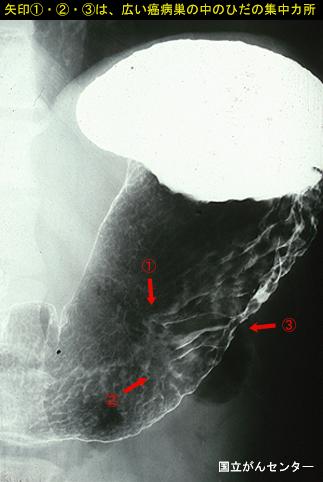

clasificación del pacienteTumor Epitelial Maligno/Adenocarcinoma

parte(separada por órganos)estómago(región)/cuerpo

método de exámenRayos X

clasificación ectoscópica de tumoresTipo 0(tipo superficial)/Tipo IIb(IIb+IIc)

diámetro mayor del tumor40 -

grado de penetraciónsm